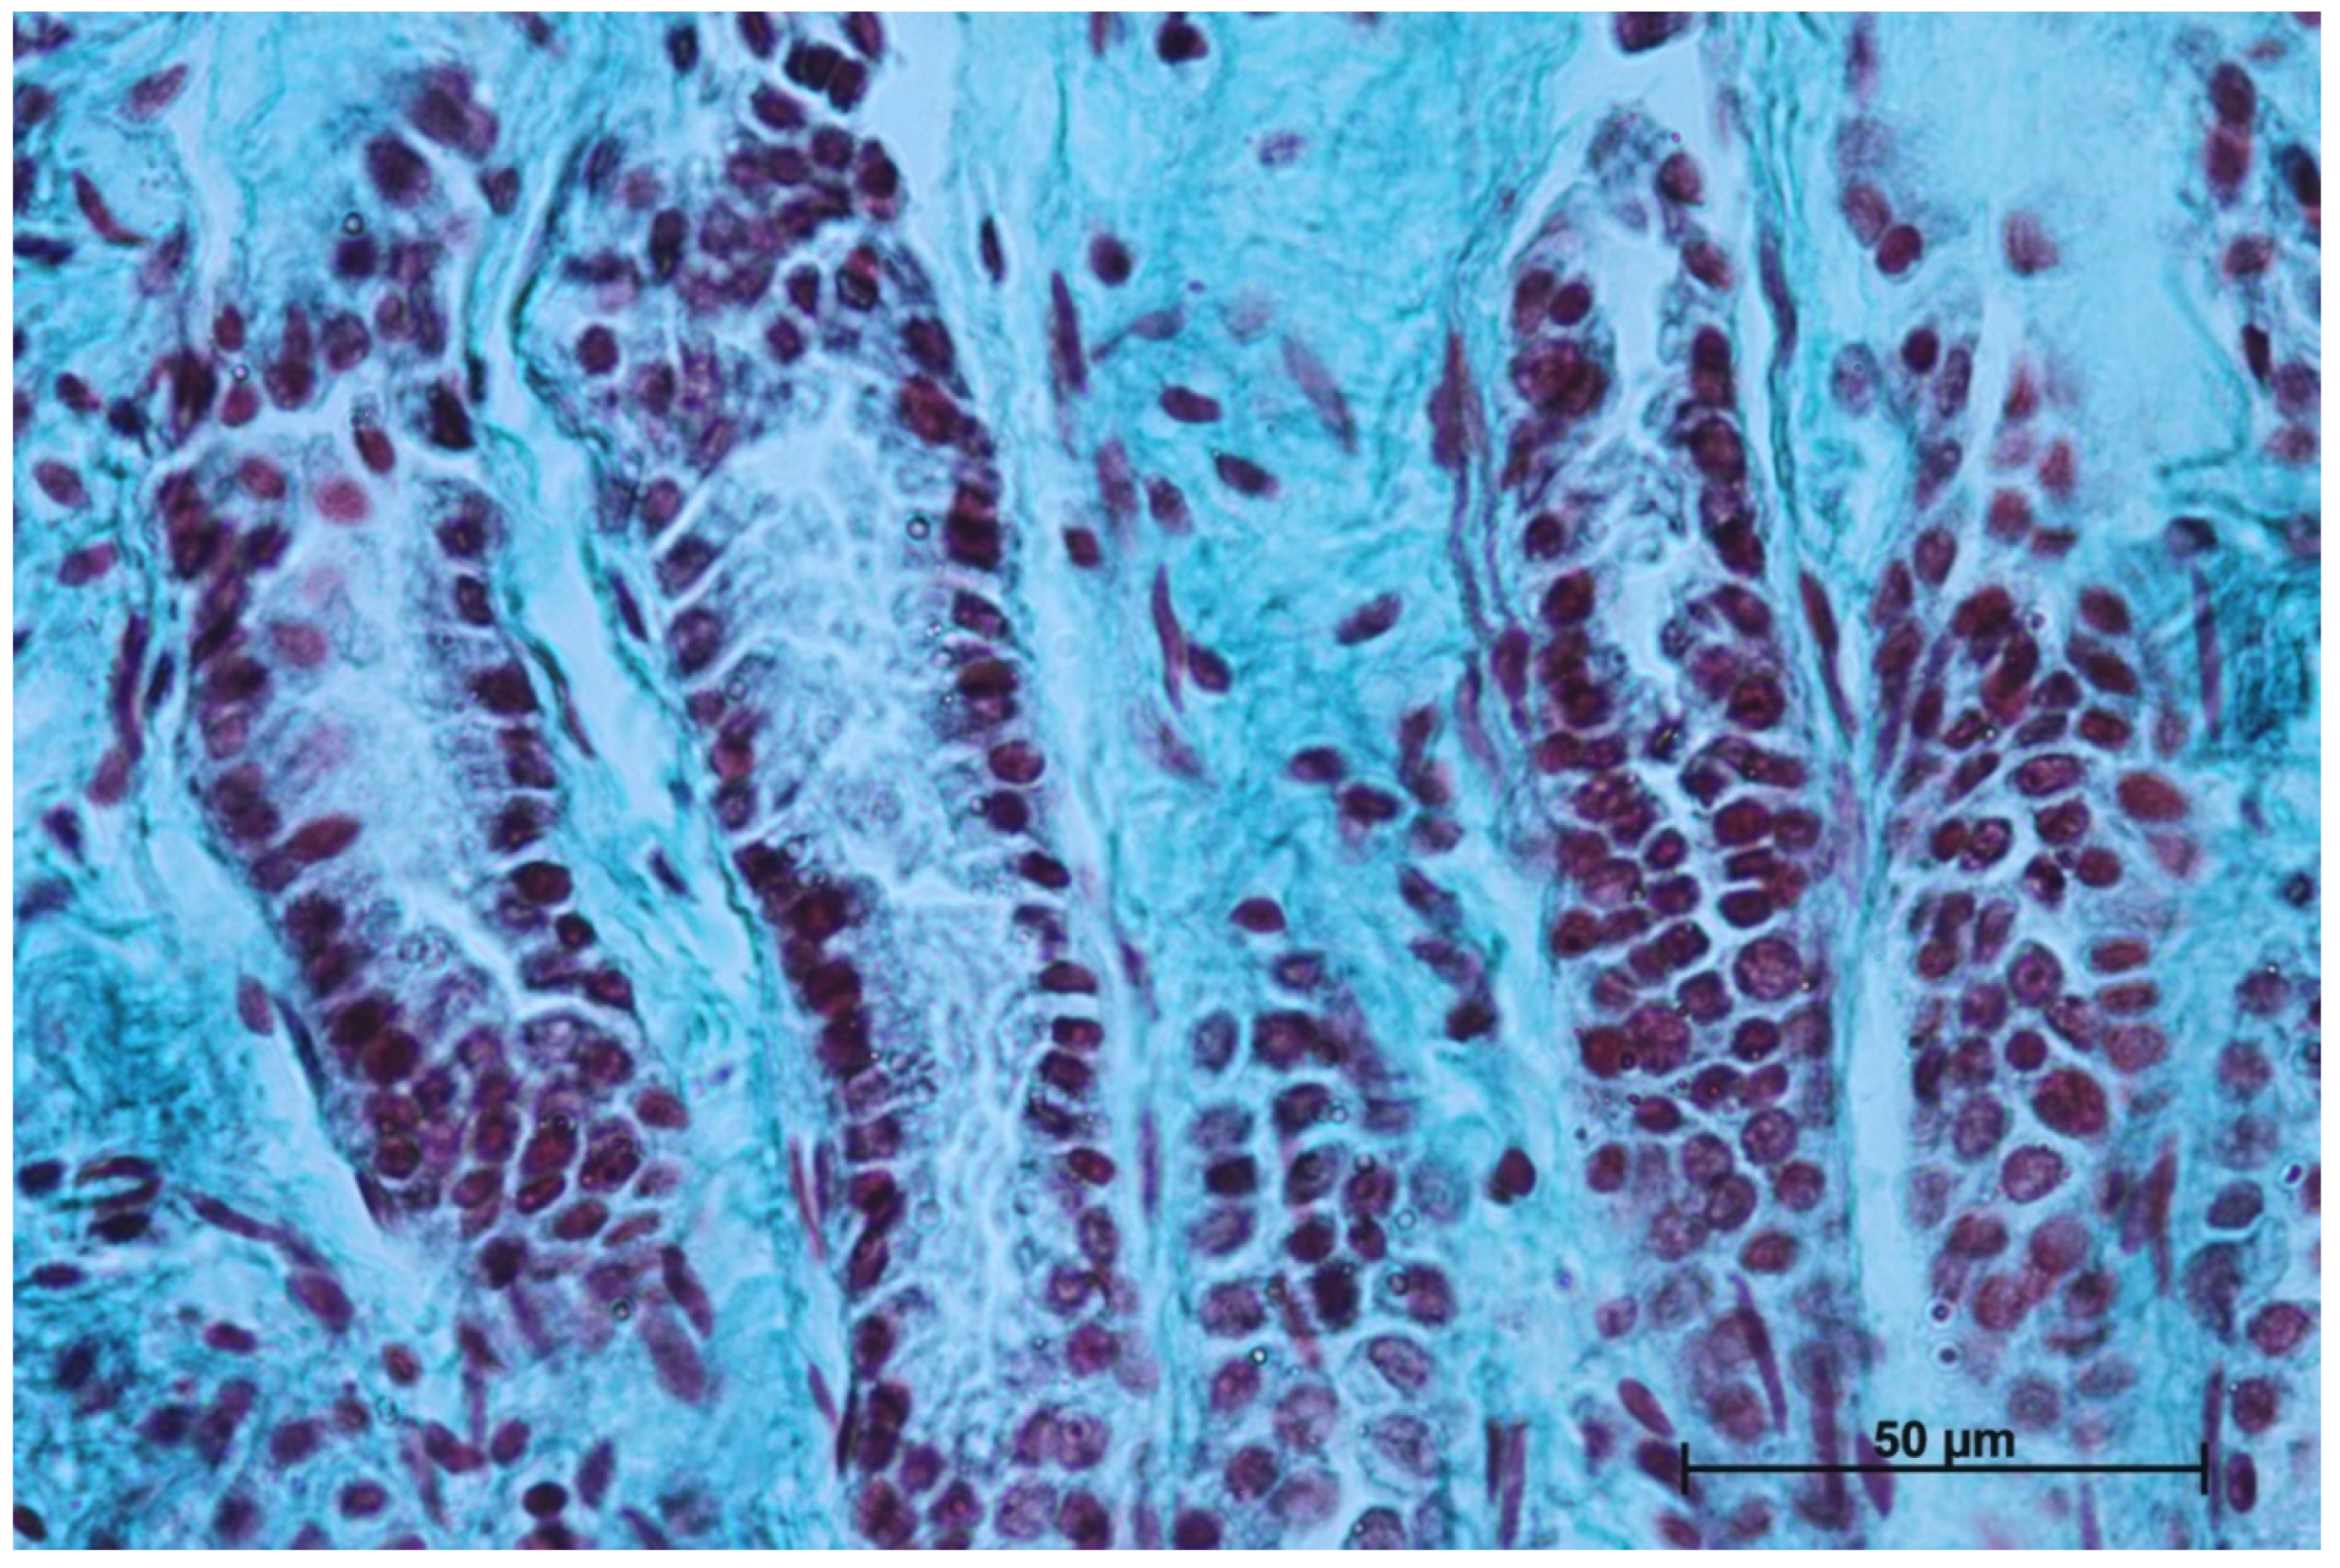

3.1. Microanatomy of the Stomach

3.5. Body of the Stomach

3.6. The Pyloric Part